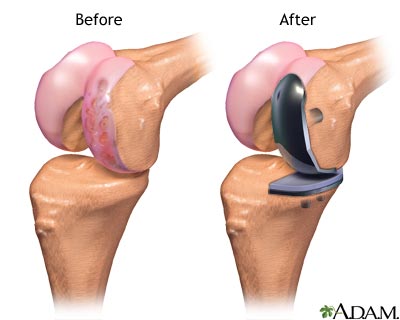

A partial knee replacement is surgery to replace only one part of a damaged knee. It can replace either the inside (medial) part, the outside (lateral) part, or the kneecap part of the knee.

Partial knee replacement surgery removes damaged tissue and bone in the knee joint. It is done when arthritis is affecting primarily only one part of the knee. The areas are replaced with an artificial implant, called a prosthetic. The rest of your knee is preserved. Partial knee replacements are most often done with smaller incisions, so there is less recovery time.

- The damaged bone and tissue are removed.

- A part made from plastic and metal is placed into the knee.